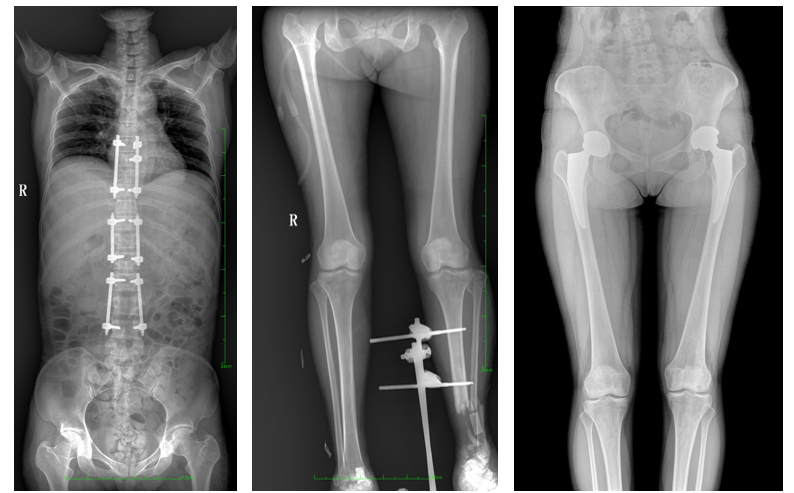

一、成像面積大。17"*34"有效視野,一次成像不拼接。相較于多張攝影再軟件拼接的DR設備,大視野平板動態DR解決了拼接圖像存在密度不均勻,拼接處圖像配準和放大效應等問題,給臨床帶來了大視野影像解決方案,可一次性覆蓋全脊柱或雙下肢影像。

如:全脊柱狀態評估、長骨關節活動度、下肢靜脈造影瓣膜功能評估、消化道功能評估、脊髓造影等更多大視野臨床應用,多面手給醫生更多驚喜。

PLX8600大視野平板動態DR可在低輻射劑量下獲得患者站立位、臥位的高質量影像。搭載自主研發的圖像均衡處理系統,能夠很好的均衡人體不同厚度組織的影像,視野大,圖像清晰,層次豐富。